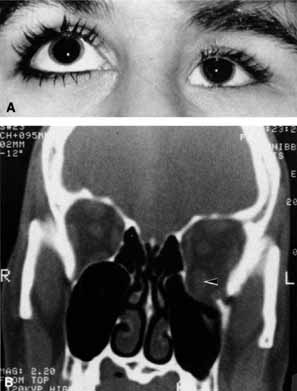

Pupillary dilation and reduction of accommodation occur when parasympathetic innervation to the globe is damaged. When the damage occurs at or distal to the ciliary ganglion, Adie's pupil results. The pupil contracts poorly to light but better to accommodation. The pupil movements are slow and poorly coordinated (vermiform). Generally there is a reduction in accommodation range. The pupil in such cases develops a supersensitivity to parasympathomimetics such as 0.1% pilocarpine. Orbital trauma, inflammation, and intraocular laser treatment may result in Adie's pupil. Deep orbital dissection lateral to the optic nerve in the region of the ciliary ganglion or around the anterior optic nerve where the short ciliary nerves run may also produce Adie's pupil. The denervation may only be sectoral, resulting in an abnormally contoured pupil which demonstrates slow tonic contracture only in the involved sector. Because the parasympathetics have diverged from cranial nerve III prior to entering the ciliary ganglion, pupillary dilation which contracts with 0.1% pilocarpine is not usually associated with neurogenic ophthalmoplegia (Fig. 19).

Fig. 19 A. A patient underwent endoscopic exploration of the right ethmoid and maxillary sinus for persistent epistaxis. Postoperatively the patient demonstrates right proptosis, restricted extraocular movements of the right eye, and a dilated right pupil. Instillation of 0.1% pilocarpine resulted in miosis on the right and no change on the left. Computed tomography (CT) shows a vessel clip lateral to the optic nerve (arrow), near the position of the ciliary ganglion. B. Coronal CT scan showing the clip lateral to the optic nerve (arrow).